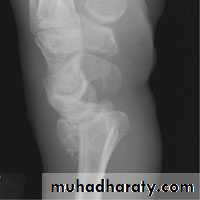

It is a transverse fracture of the distal end of the radius with posterior displacement of the distal fragment.

X-ray : there is transverse fracture of the radius at the cortico – cancellous junction , and the distal fragment is displaced posteriorly ; some time it is severely comminuted or crushed